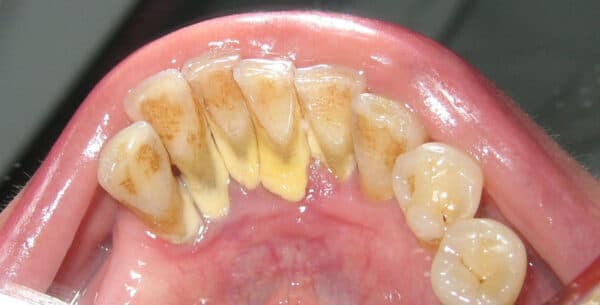

Vôi răng, mảng bám tích tụ trên răng gây nên nhiều bệnh lý răng miệng

Vôi răng còn được biết đến với tên gọi phổ biến hơn chính là cao răng. Vôi răng được hình thành do tác động của vi khuẩn lên các thức ăn còn sót lại, chưa được loại bỏ hết. Trải qua nhiều ngày tích tụ, chúng sẽ dần bám chặt ở đường nướu hoặc là được dưới nướu. Nếu không được xử lý loại bỏ, các mảng bám vôi răng có thể gây hệ quả kích ứng mô nướu. Nhiều trường hợp cao răng không được loại bỏ còn góp phần tăng thêm diện tích cho các mảng bám phát triển, bám chặt hơn và gây nên các bệnh về răng miệng như: sâu răng, viêm nướu.

Cách nhận biết vôi răng rất đơn giản, nó chính là lớp có màu vàng hay nâu trên răng hoặc nướu. Không chỉ tiềm ẩn nguy cơ gây hại sức khỏe răng miệng, mà chúng còn gây mất thẩm mỹ cho hàm răng của bạn.